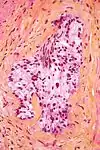

In histology, the HPS stain, or hematoxylin phloxine saffron stain, is a way of marking tissues.

HPS is similar to H&E, the standard bearer in histology. However, it differentiates between the most common connective tissue (collagen) and muscle and cytoplasm by staining the former yellow and the latter two pink,[1] unlike an H&E stain, which stains all three pink.